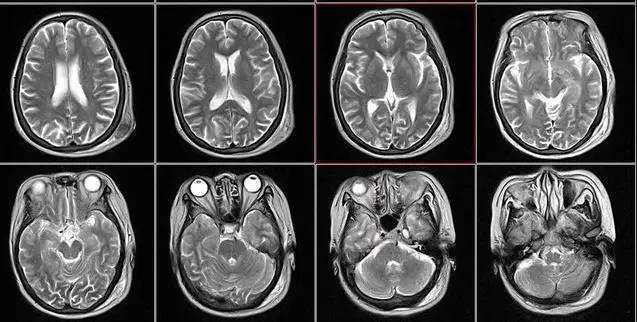

核磁共振

摇一摇再看

核磁共振仪使用较强大的磁场,使人体中所有水分子磁场的磁力线方向一致,这时磁共振机的磁场突然消失,身体中水分子的磁力线方向,突然恢复到原来随意排列的状态。简单说,就相当于用手摇一摇,让水分子振动起来,再平静下来,感受一下里面的振动。所以,核磁共振也被戏说为是摇摇看的检查。

2、颈椎腰椎——最佳选核磁,次选CT

颈椎病、腰椎间盘突出等椎间盘疾病需要观察椎间盘与相应的神经根,要想更好观察这些软组织,最优选择就是核磁。同样,对于关节、肌肉、脂肪组织检查,核磁也是首选。